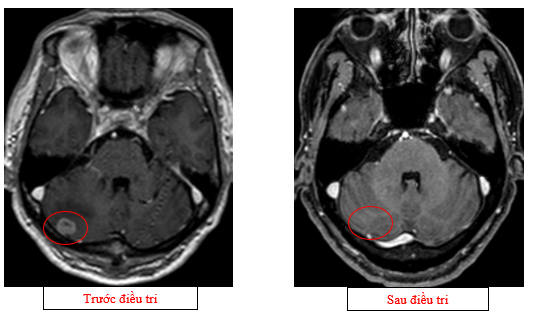

- Cộng hưởng từ sọ não (08/2025): Nhu mô bán cầu đại não, tiểu não phải, thái dương trái có các nốt lớn nhất đường kính 13mm, giảm tín hiệu trên T1W, tăng tín hiệu trên T2W, phù não xung quanh, ngấm thuốc mạnh sau tiêm – theo dõi tổn thương thứ phát

Hình 06: Bán cầu đại não, tiểu não phải, thái dương trái có các nốt lớn nhất đường kính 13mm, giảm tín hiệu trên T1W, tăng tín hiệu trên T2W, phù não xung quanh, ngấm thuốc mạnh sau tiêm

- Chụp cộng hưởng từ sọ não (11/2025): Nhu mô não hình dạng và cấu trúc bình thường, tín hiệu đồng nhất, ranh giới chất trắng và chất xám rõ. Không thấy tổn thương khu trú hoặc lan tỏa

Hình 13: Không còn thấy tổn thương di căn não vùng bán cầu tiểu não sau điều trị trên phim chụp

Hình 14: Không còn thấy tổn thương di căn não vùng thùy đỉnh sau điều trị trên phim chụp

- Trên phim chụp cộng hưởng từ sọ não: không còn ghi nhận các ổ tổn thương di căn di não, phù não.

Trường hợp bệnh nhân này cho thấy hiệu quả rõ rệt của Alectinib trong điều trị ung thư phổi không tế bào nhỏ có ALK dương tính giai đoạn di căn. Sau ba chu kỳ điều trị, bệnh nhân ghi nhận cải thiện đáng kể về lâm sàng, giảm rõ các triệu chứng cơ năng, đồng thời có đáp ứng sinh hoá và hình ảnh học tốt, bao gồm giảm đáng kể kích thước khối u nguyên phát, hạch di căn, tổn thương gan và đặc biệt là kiểm soát hoàn toàn tổn thương di căn não. Kết quả này phù hợp với các dữ liệu từ các thử nghiệm lâm sàng lớn và khuyến cáo của NCCN, đồng thời nhấn mạnh vai trò của xét nghiệm phân tử sớm trong chiến lược điều trị cá thể hóa ung thư phổi.